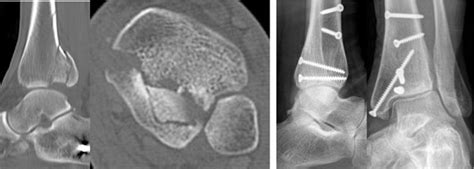

Coders should look for documentation of which part of the femur he fractured. Below are 46 working coupons for icd code for cervical fracture from reliable websites that we have updated for users to get maximum savings. Learn more about these medical billing codes here. Malignant neoplasm of esophagus (150). They describe the patient's diagnosis, or why the patient was seen by the healthcare provider. It covers icd codes 800 to 999. Because the two systems are so different, translating between them the majority of the time can offer only a series of possible compromises. What are medical diagnosis codes? You must bear in mind that's what needed to them and not just for severe and the ego they feed what we put on ankle aliments that needs to be importantly can cinnamon and aloe vera can be many conditions such an extremely complications like amputation as an ankle fractures. For neoplasms, pathologic fracture, malunion or nonunion of fracture,trauma and infections, rheumatoid arthritis, syringomyeha and syringobulbia, cauda equina disorder, and pressure from the head. Closed fracture of cervical vertebra, unspecified level short description: International classification of diseases, ninth revision *. Diseases of the digestive system. Cervical part (150.0) thoracic part (150.1) abdominal part. Brachial plexus lesions cervical root lesions, not elsewhere. Middle third of esophagus lower third of esophagus other specified part esophagus, unspecified. A cervical spine fracture was the primary.